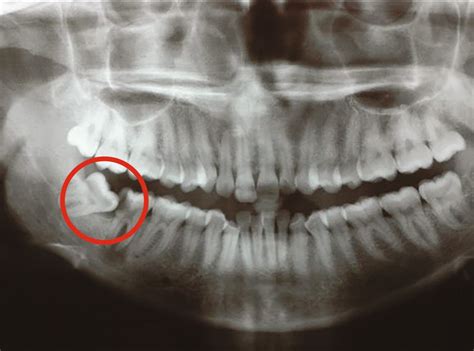

problems from wisdom teeth